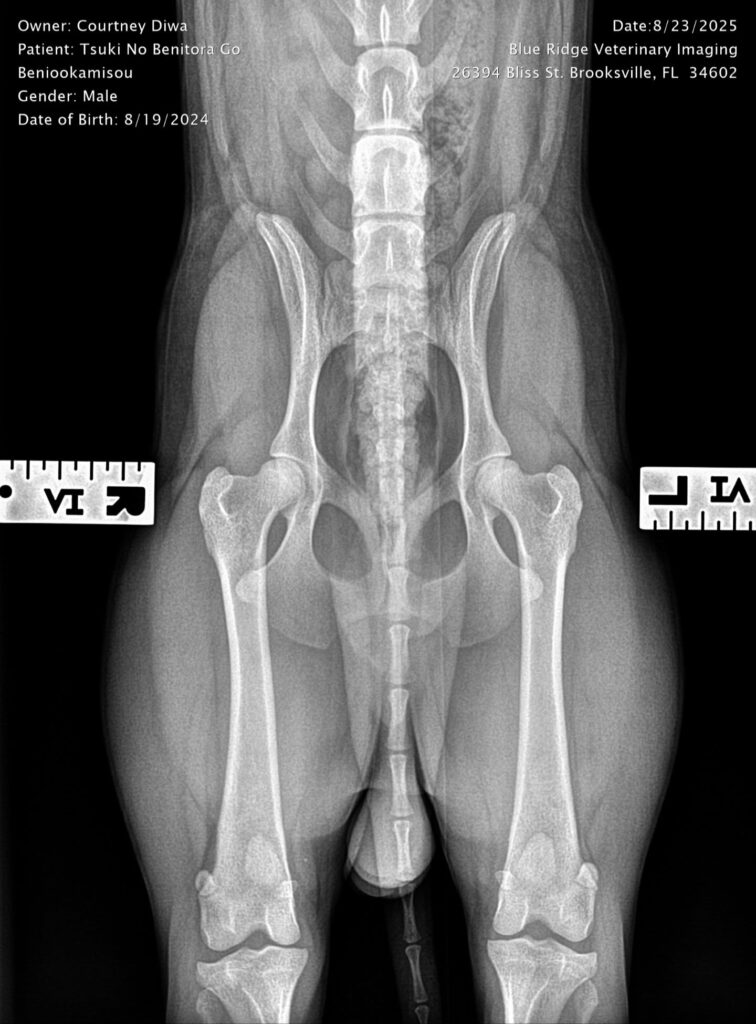

Titles & Health Certificates